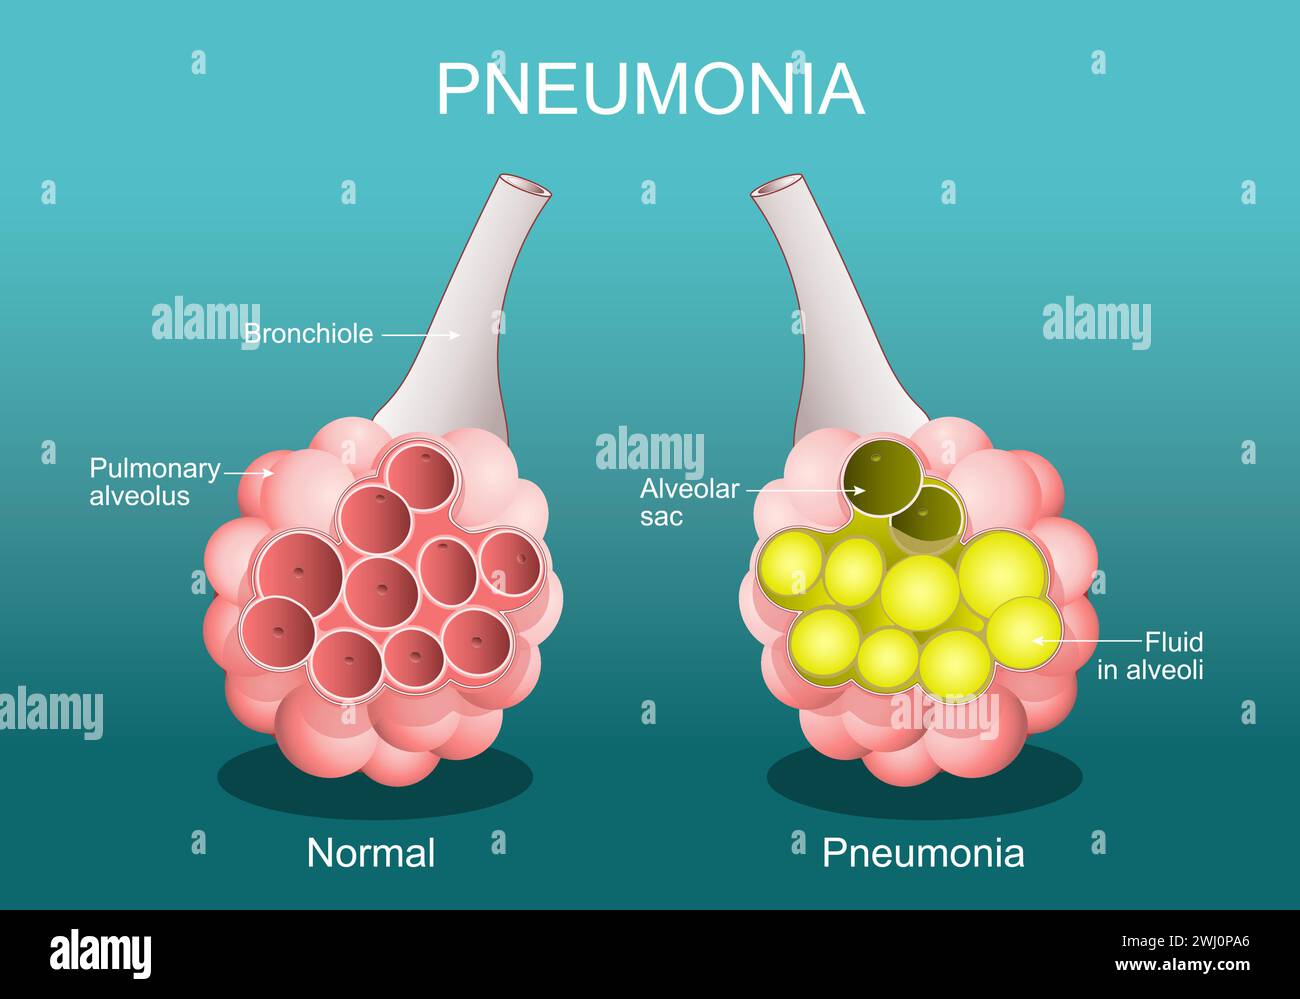

RF2WJ0PA6–Pneumonie. Etat inflammatoire des poumons. La section transversale de l'alvéole normale et les alvéoles sont remplies de liquides. Affiche vectorielle. Plat isométrique

RF2A86M1N–La pneumonie et alvéoles pulmonaires de liquide ou de l'anatomie de l'inflammation alvéolaire du schéma d'un concept médical anatomie pulmonaire et respiratoire.

RF2A895XN–La pneumonie et alvéoles pulmonaires avec schéma fluide ou inflammation alvéolaire schéma anatomique comme un concept médical des poumons sains et malsains.